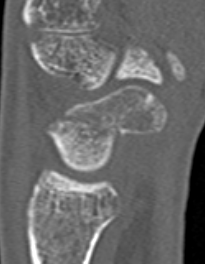

CT

Indication: any potential displacement

Position: patient prone with fully pronated hand over head

Instability

- displacement > 1mm on any film

- intra-scaphoid angle > 35o

- comminution

- proximal pole fractures

- perilunate trans-scaphoid dislocation

Scaphoid waist fracture 1 mm displaced

Scaphoid fracture with significant displacement

Scaphoid proximal pole fracture